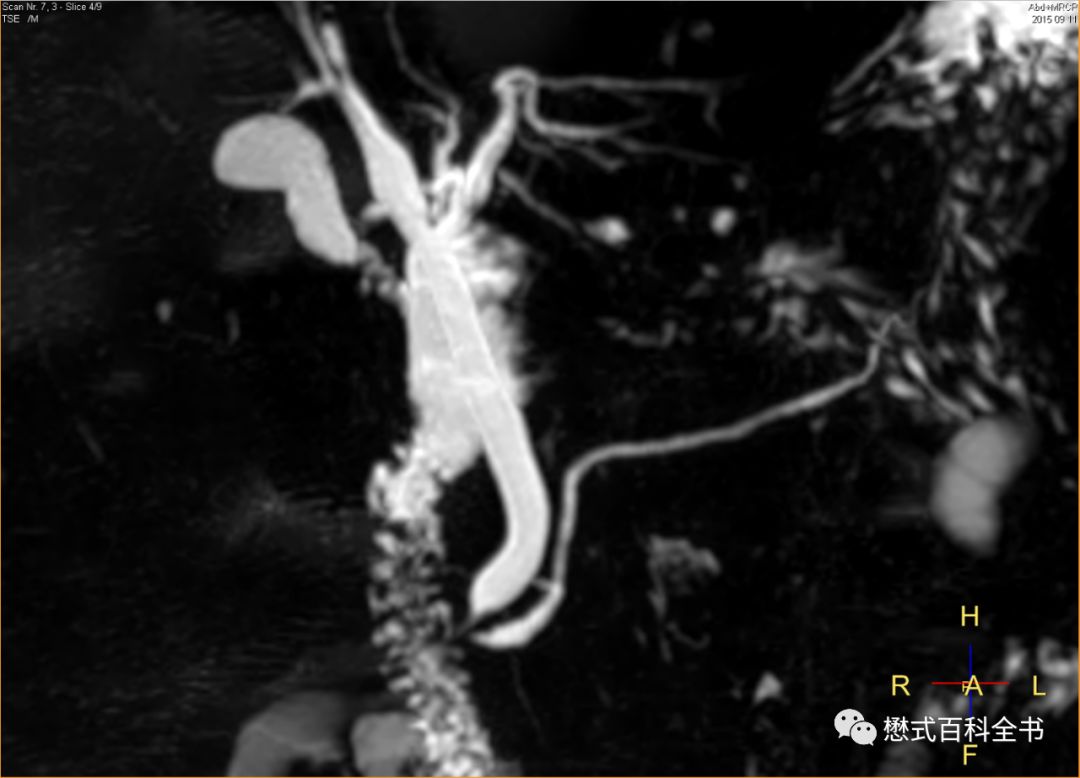

图9:MRCP注意看图中标记的线

有时候,我们组MRCP经常能看到一根比较亮的线竖着穿过胰管。有老师认为是伪影,有老师认为是其他结构。看了一些文献,有的说这个是淋巴管,扫描MRCP出现这个的概率不多。还有文献说和人种有关系,貌似中国人出现这个多。这个位置看着是胸导管?(我们专门有针对胸导管成像的序列,效果非常好)对于这个问题,我也没有过多研究,看看老师们有什么高见,可以留言。

图10-13:飞利浦专业胸导管成像序列